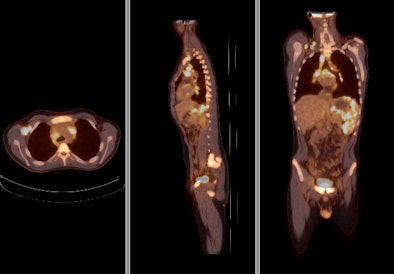

![]() |

| Above, PET and PET/CT fused data post-therapy for lymphoma. Below, PET and PET/CT fused data pretherapy for lymphoma. The images illustrate a patient's lymphoma staging to assess initial treatment strategy and follow-up study after initial treatment to plan subsequent treatment. The images were taken by Philips Healthcare's Gemini TF with time-of-flight. Images courtesy of Philips and University Hospitals Case Medical Center in Cleveland. |